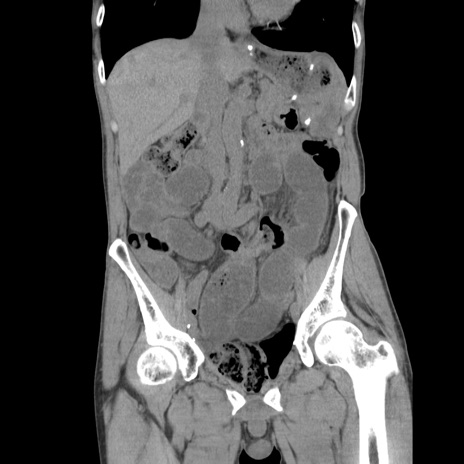

症例11(冠状断像)

【症例】 60歳代男性

【主訴】 下腹部痛

【現病歴】 本日夜中より下腹部痛の症状認め、受診。

【既往歴】 膀胱癌(膀胱全摘+尿管皮膚瘻術) 、胃癌術後

【身体所見】 BT 35.3℃、PR 58/min、BP 136/98mHg、腹部平坦、軟、腸蠕動音±、ストマ留置あり、左上腹部~正中部に圧痛あり、反跳痛なし。

【データ】WBC 5100、CRP0.01